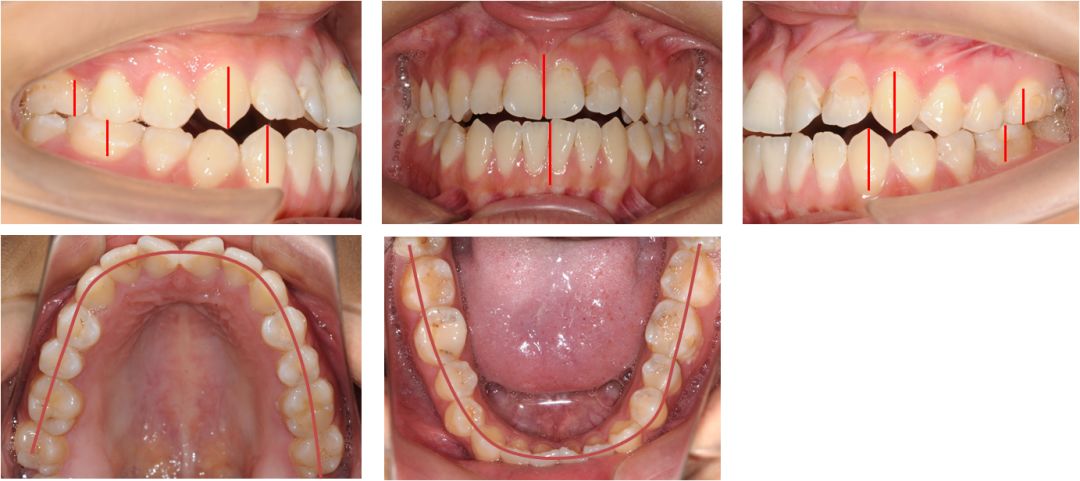

口腔检查:

上下牙弓呈方圆形;双侧尖牙、磨牙III类关系;21牙与31牙呈切合;前牙呈现约1 mm的局部开合;下颌中线较上颌中线左偏1 mm。

模型分析:

上颌拥挤度:1.5 mm,下颌拥挤度:1.5 mm。Bolton指数:全牙比为86.70%,前牙比为75.5%。患者上下颌牙列均存在前牙段轻度的拥挤,前牙和全牙的bolton指数均偏小,提示上颌牙齿牙冠宽度偏大。